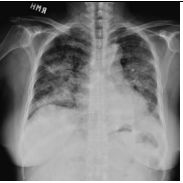

2. A 27-year-old woman had productive cough for one month.